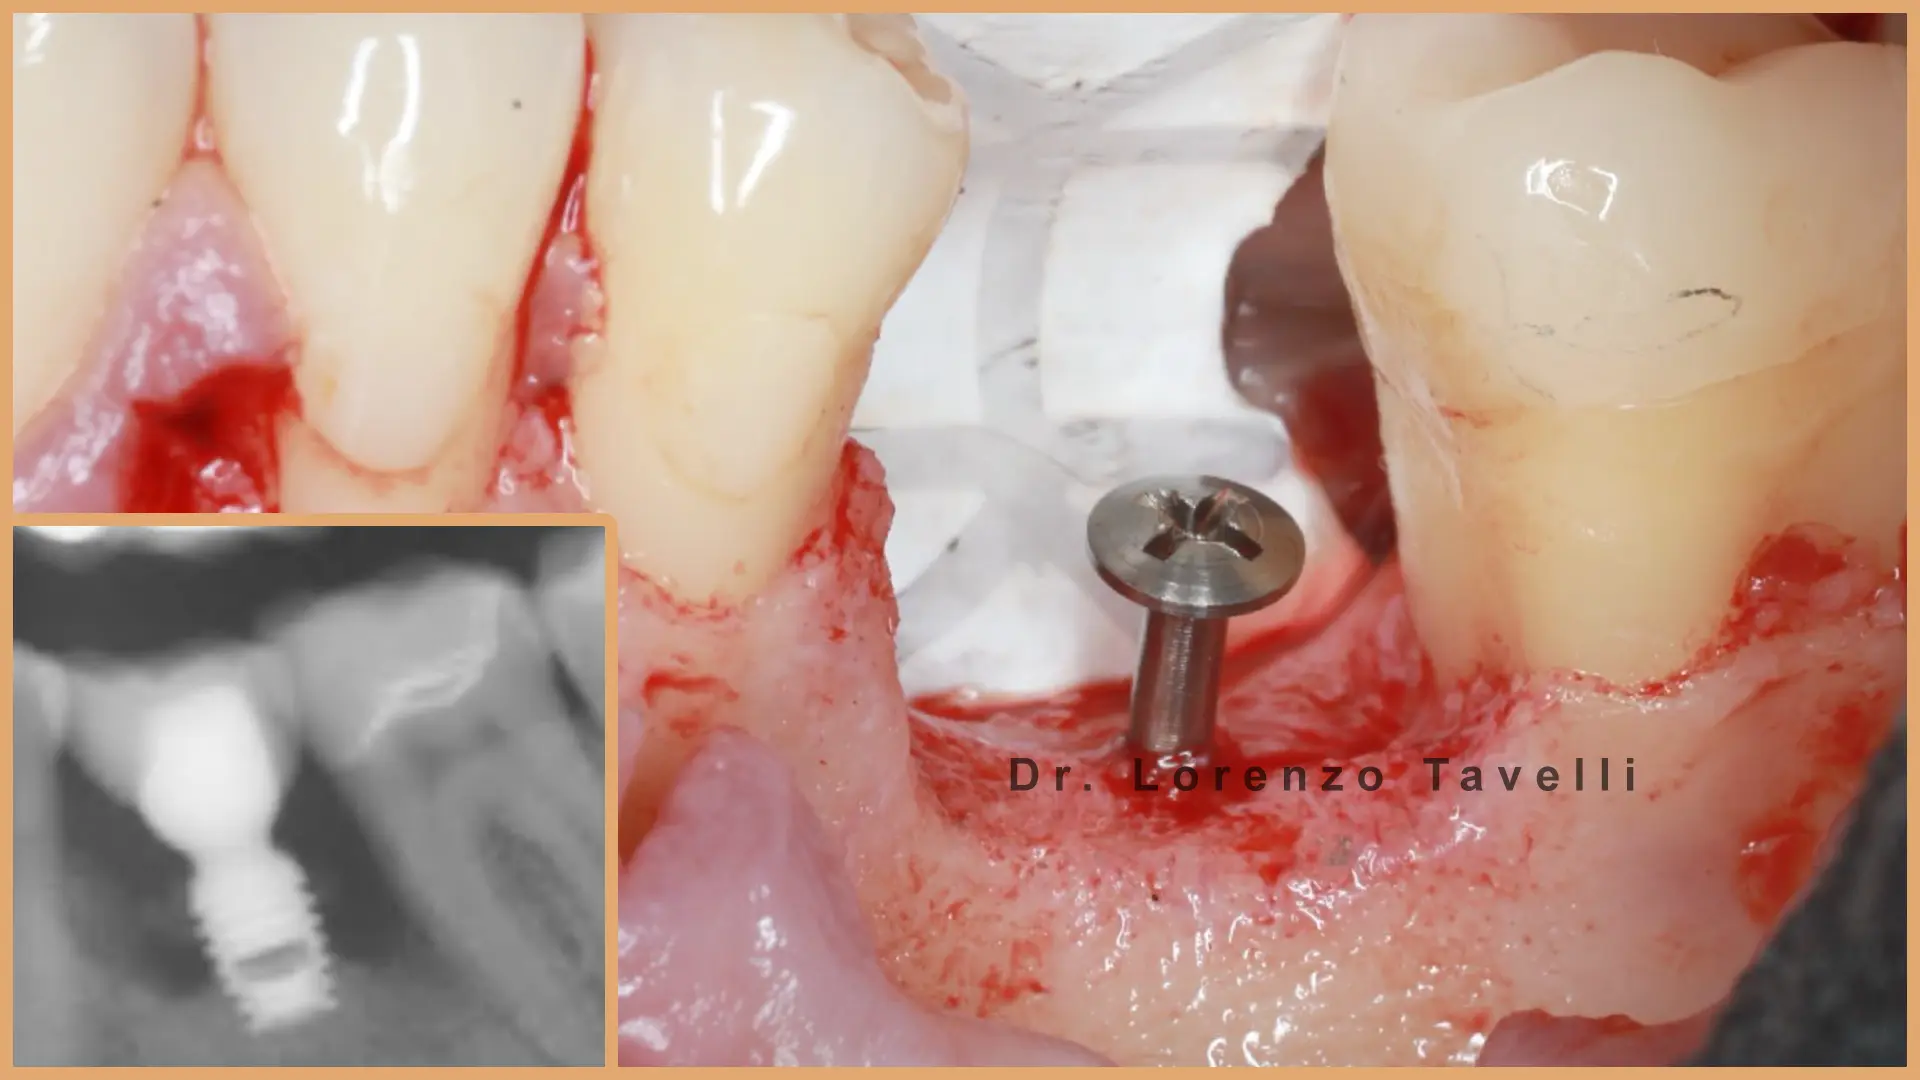

Prin prelegeri susținute de experți, videoclipuri chirurgicale și instruire practică (hands-on), participanții vor explora tehnici moderne de augmentare a țesuturilor moi, gestionarea fenotipului peri-implantar, prevenirea complicațiilor și protocoale avansate de grefare. O atenție deosebită este acordată tehnicilor minim invazive și de tip tunel, reconstrucției papilei și cazurilor complexe de implanturi în zona anterioară.

Atelierele noastre practice oferă participanților oportunitatea de a exersa tehnici contemporane de augmentare a țesuturilor moi și de grefare, sub îndrumarea experților. Prin sesiuni etapizate, aliniate cu scenarii clinice reale, participanții vor perfecționa abordările minim invazive și cele de tip tunel, reconstrucția papilei, gestionarea țesutului moale peri-implantar.

Acest curs este conceput special pentru clinicienii care doresc să își perfecționeze expertiza în implantologia estetică. Programul integrează în mod unic dovezile științifice cu aplicațiile practice, oferind o perspectivă exclusivă asupra unor cazuri clinice complexe prezentate de Dr. Lorenzo Tavelli, ce oferă o viziune aprofundată asupra parcursului său chirurgical personal și modul în care se iau cele mai bune decizii. La finalul cursului, veți dobândi un arsenal chirurgical extins și abilitățile necesare pentru a gestiona chiar și cele mai provocatoare situații în implantologie!